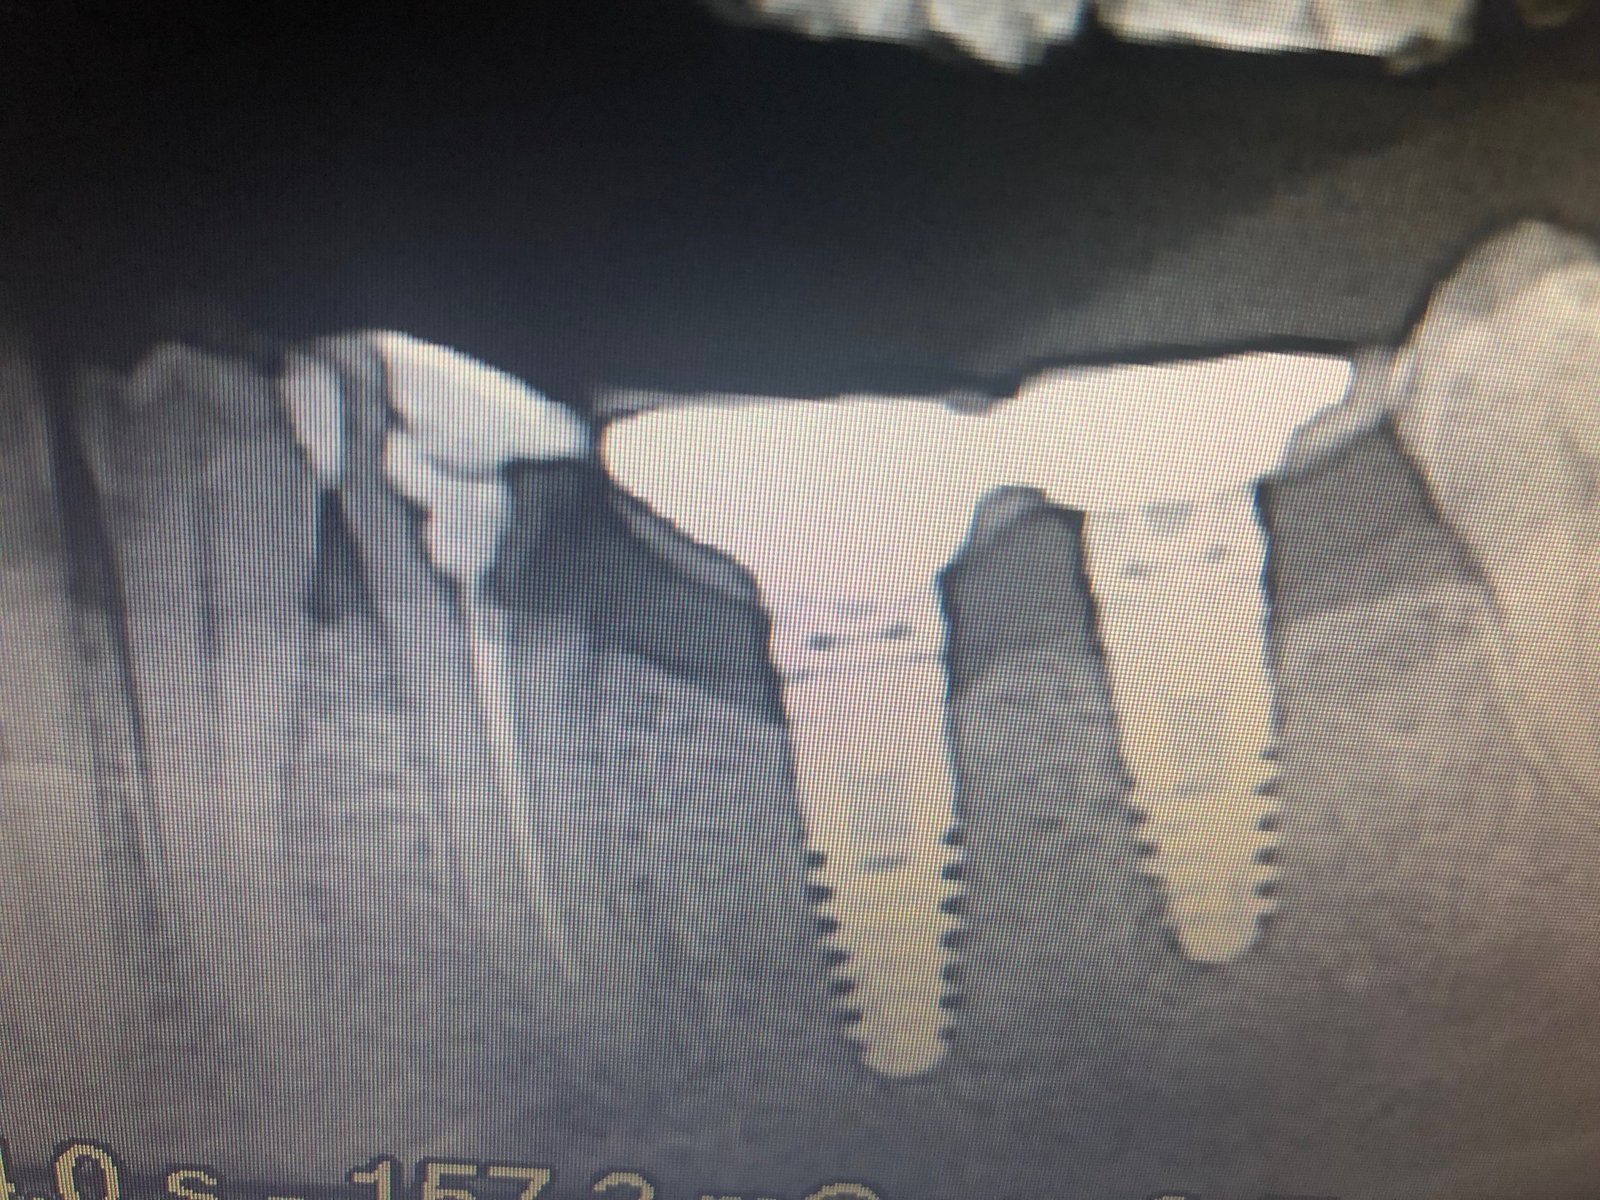

qué implantes son #46, #47, #41 y #31???

Paciente acude a clínica con implantes inferiores sin cargar. Conocemos el tipo de implante que está en posición de #33 y #43 , los otros implantes ( #46, #47, #41 [...]